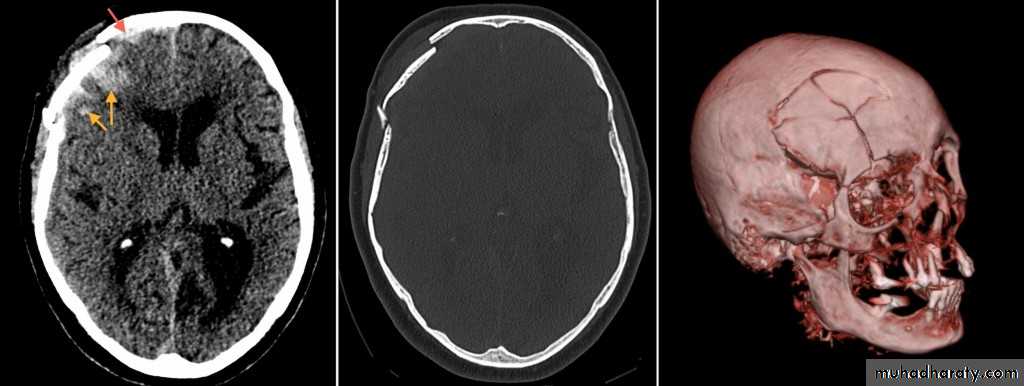

Common CT findings of traumatic brain injury